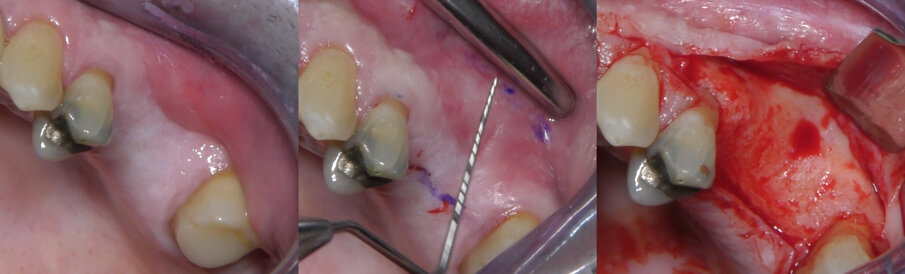

Per ottenere un accesso migliore all’area chirurgica è stato impiegato un apribocca flessibile (Optragate, Ivoclar Vivadent AG, Schaan, Liechtenstein). L’area di intervento è stata anestetizzata utilizzando articaina cloridrato 40 mg con adrenalina 1:100000. Si è proceduto quindi a sollevare un lembo a tutto spessore (Fig. 4). L’incisione mesiale è stata eseguita secondo la tecnica della papilla preservation al fine di conservare la gengiva aderente; non sono state eseguite incisioni di rilascio né distali né mesiali. Utilizzando la guida chirurgica, si è riportato il disegno della finestra d’accesso sulla parete vestibolare utilizzando una matita dermografica. L’osteotomia è stata eseguita utilizzando inserti piezoelettrici; la membrana sinusale è stata quindi scollata e sollevata (Fig. 5).

Fig. 4 - Aspetto clinico del mascellare posteriore sinistro e disegno del lembo. Viene eseguita una sola incisione sul versante occlusale e mediale della cresta, preservando la papilla dell’elemento residuo più distale. Non si eseguono incisioni di scarico; viene sollevato un lembo a tutto spessore.

Fig. 5 - La preparazione dell’antrostomia e lo scollamento e sollevamento della membrana sinusale. Dopo avere disegnato l’antrostomia sulla parete vestibolare, si procede alla sua esecuzione e al sollevamento della membrana.